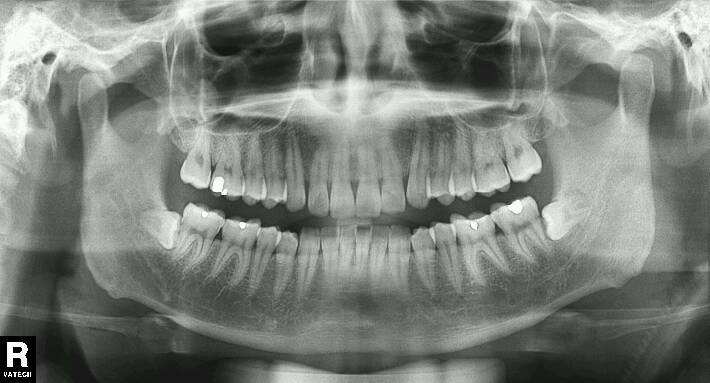

还是这种不要脸的,沉睡在牙槽骨里的。

只要长歪了,只要没长正,都会带来隐患,给你的未来带来无限的烦恼和较大的经济负担。